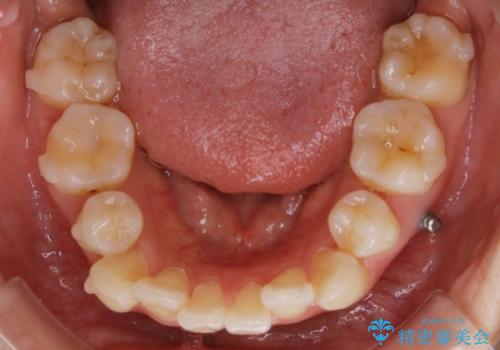

- 以前、中学生から高校生にかけてワイヤー装置による抜歯矯正を経験されている患者さんで、大人になってからのライフスタイルの変化でリテーナーを継続使用することができず、ガタつきが目立つようになってきてしまったのでもう一度矯正治療がしたいという主訴でご来院されました。

既に上下左右の4番目の歯が抜歯されているため、今回の治療では抜歯をせず歯の移動だけでガタつきを治す必要があり難易度が高くなっていました。